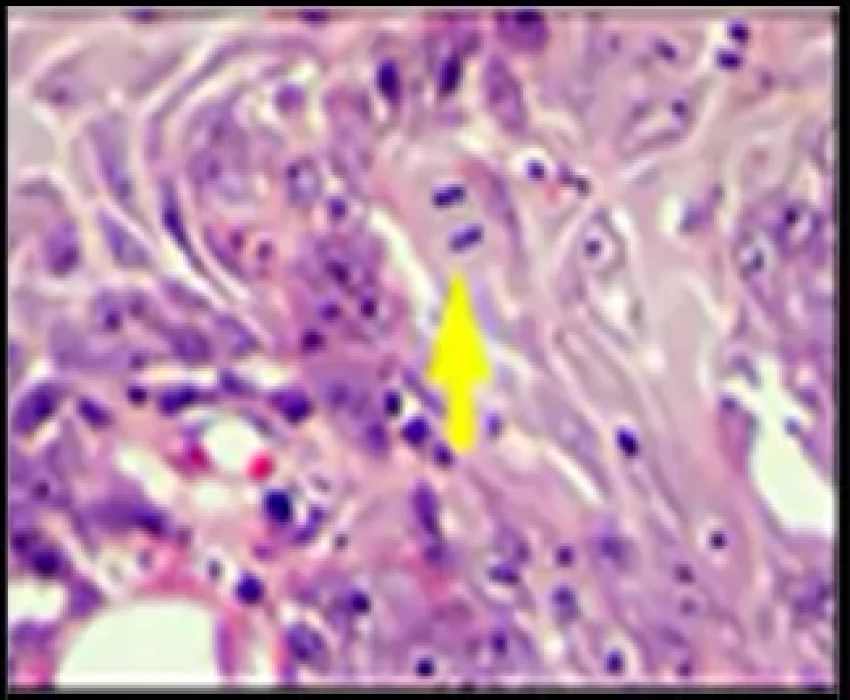

Routinely, haematoxylin and eosin stain is used for the estimation of mitotic figures but the distinction between a pyknotic nucleus, an apoptotic cell and a mitotic cell in a routinely stained tissue section may pose a problem. Errors in identifying a mitotic cell can thus weaken the reliability of histological grading due to the loose use of morphologic criteria. Thus, this study was conducted to evaluate the efficacy of various stains like Haematoxylin and Eosin, Crystal Violet, Toluidine Blue, Feulgen and Giemsa to stain mitotic figures.

Feulgen was found to be the best stain for identification of mitotic figures and should be used in routine staining to count mitotic figures, thus, in turn giving an insight into the aggressiveness of the lesion.